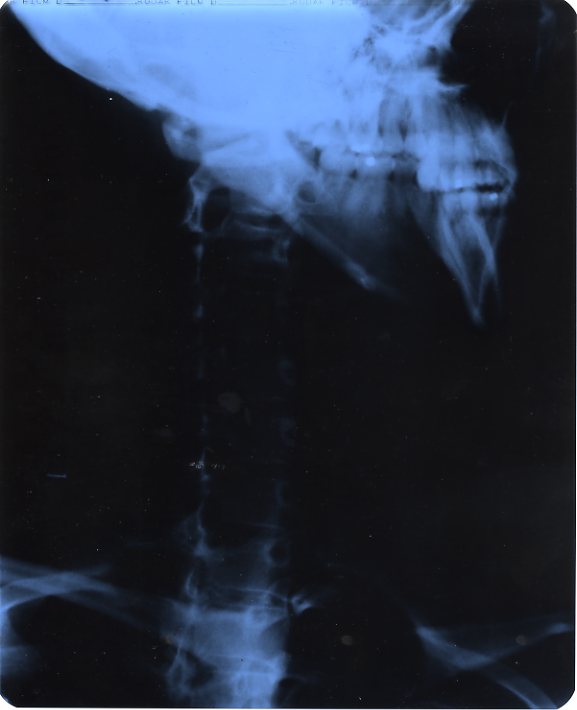

My Mom decides to send me to the Orthopedics hospital since they specialize in stuff like carpal tunnel. I get x-rays, cat scanned up and they determine that my neck is too straight. I’ve lost my natural curvature in the vertebrae of my neck causing pressure on my nerves, therefor giving me carpal tunnel.

Straight as an Arrow